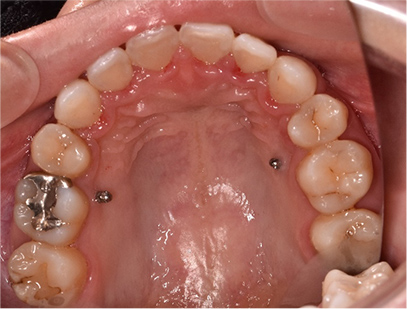

症例02

前歯が出ている症例

上下の前歯が出ていることを主訴として来院されました。 通常どおりの検査を行い、「上下顎前突」と診断されました。

治療計画

上の歯は前から数えて左右の4番目の歯を、下の歯は左下は4番目右下は5番目の歯を抜歯してそのスペースを利用して前歯を内側に動かすことにしました。

矯正の種類

上は裏側矯正

下は表側からの白い矯正装置(セラミック)

治療前

• 矯正治療前の横顔

• 上側

• 下側